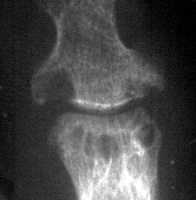

Septic Arthritis: Joint space narrowing and erosions

++

++ + +